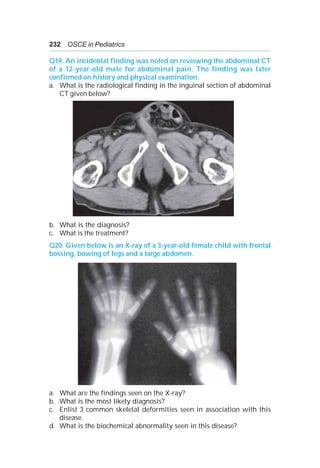

Oral α-tocopherol or TPGS 50-400 IU/day.

25-hydroxycholecalciferol 3-5 μg/kg/day or D2 5,000–8,000 IU/day.

Water-soluble derivative of menadione 2.5-5.0 mg every other day.

Calcium, phosphate, or zinc supplementation.

Choleretic bile acids and ursodeoxycholic acid, 15-20 mg/kg/day.

Dietary formula or supplements containing medium-chain triglycerides.